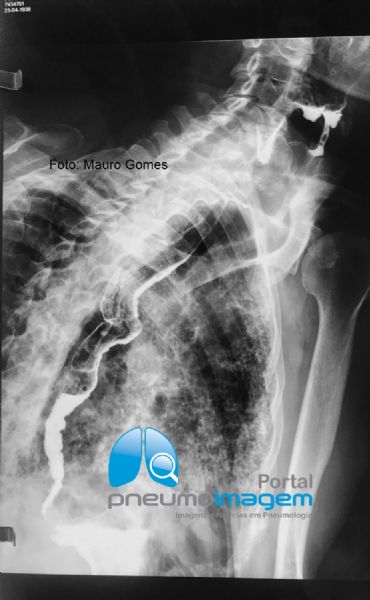

Na ausência de pneumonia intersticial usual, a associação mais frequente é com aspiração ácida recorrente. Nesses casos, os pacientes costumam ser mais velhos (idade média de 79 anos) e a maioria possui Doença do Refluxo Gastroesofágico (DRGE - 75%), Apneia Obstrutiva do Sono (SAOS) ou uma condição neurológica debilitante. Nesse caso, observe no exame contrastado do esôfago, estômago e duodeno (EED) o peristaltismo esofágico reduzido e incoordenado, com ondas terciárias e esvaziamento lento, o que provoca estase na luz do órgão e favorece aspiração para os pulmões.

In the absence of usual interstitial pneumonia, the most frequent association is with recurrent acid aspiration. In these cases, patients are usually older (mean age 79 years) and most have Gastroesophageal Reflux Disease (GERD - 75%), Obstructive Sleep Apnea (OSA) or a debilitating neurological condition. In this case, observe in the contrasted examination of the esophagus, stomach and duodenum the reduced and uncoordinated esophageal peristalsis, with tertiary waves and slow emptying, which causes stasis in the organ lumen and favors aspiration to the lungs.